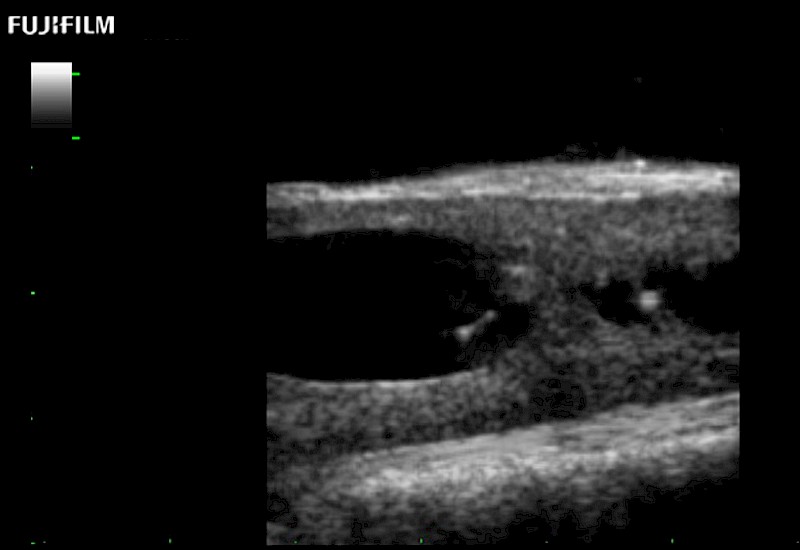

Hockey-stick linear array transducer is the transducer of choice for cervical spine scanning.

Main Specifications: